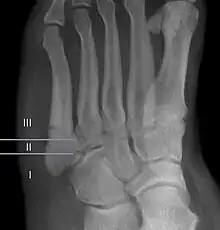

For several reasons, a Jones fracture may not unite. The diaphyseal bone (zone II), where the fracture occurs, is an area of potentially poor blood supply, existing in a watershed area between two blood supplies,[14] this may compromise healing. In addition, there are various tendons, including the peroneus brevis and fibularis tertius; these may pull the fracture apart and prevent healing.[24]

Zones I has been associated with relatively guaranteed union and this union has taken place with only limited restriction of activity combined with early immobilization. On the other hand, zone II has been associated with either delayed or non-union and, consequently, it has been generally agreed that fractures in this area should be considered for some form of internal immobilization, such as internal screw fixation.[25]

These zones can be identified anatomically and on x-ray adding to the clinical usefulness of this classification.[26] Surgical intervention is not, by itself, a guarantee of cure and has its own complication rate. Other reviews of the literature have concluded that conservative, non-operative, treatment is an acceptable option for the non-athlete.[27]

-

Anatomy of the fifth metatarsal. -

3 zone description -